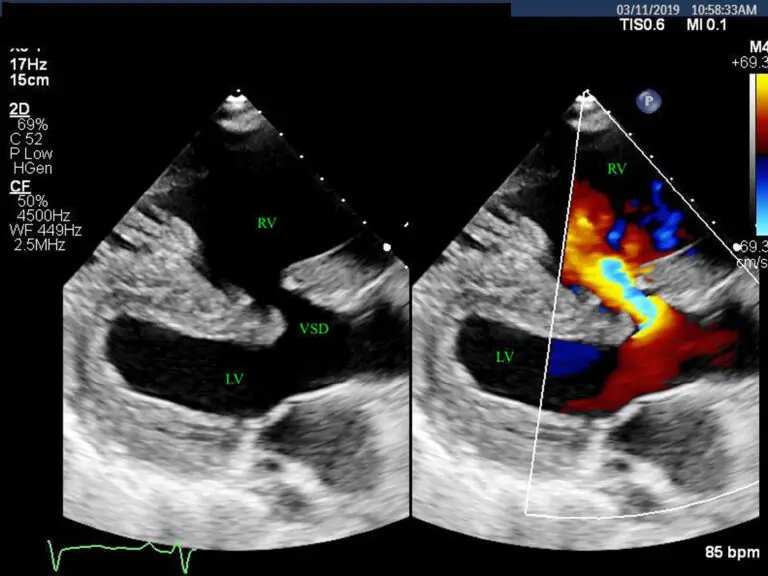

Voici un article destiné à ton blog vétérinaire sur les communications interventriculaires (CIV) chez le…